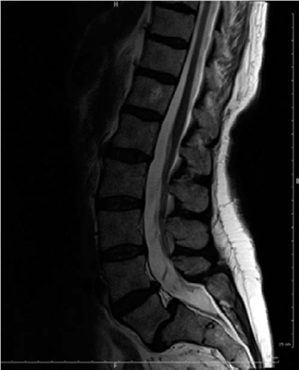

Spine structured oral questions5: Lumbar spinal stenosis and cervical myelopathy EXAMINER : A 70-year-old lad…